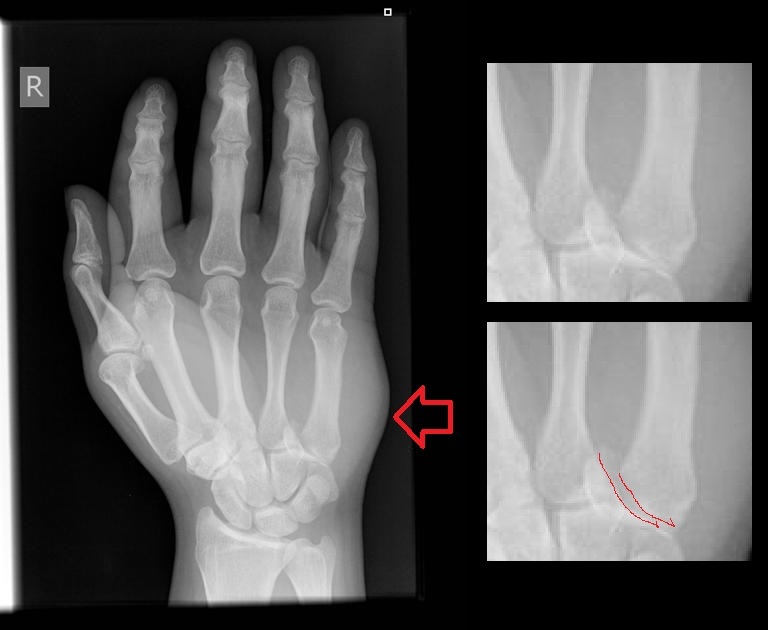

Most common metacarpal fracture? Most common anatomic location?

5th MC Neck of MC

Boxer’s fracture?

Base of 5th MC